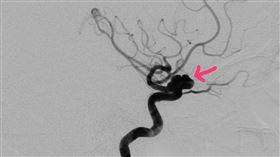

健身女腦動脈瘤破裂昏迷 典型症狀曝

台中烏日World Gym昨(15)日一名女會員健身...

昏迷指數6 蔡同榮腦中風開刀病危

前民進黨立委蔡同榮今(18)日上午突然腦中風,傳傭人...